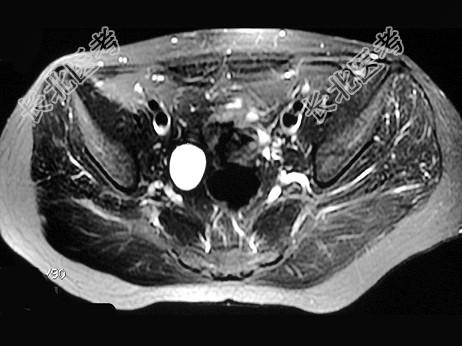

多项选择题女,31岁, 右侧腰部胀痛不适,MRI检查如图所示, 下列说法正确的是 ( )

A、右肾重度积水

B、右侧输尿管粗细不均并迂曲扩张

C、右侧输尿管下段呈囊样扩张

D、左肾输尿管未见异常

E、考虑为右侧输尿管囊肿